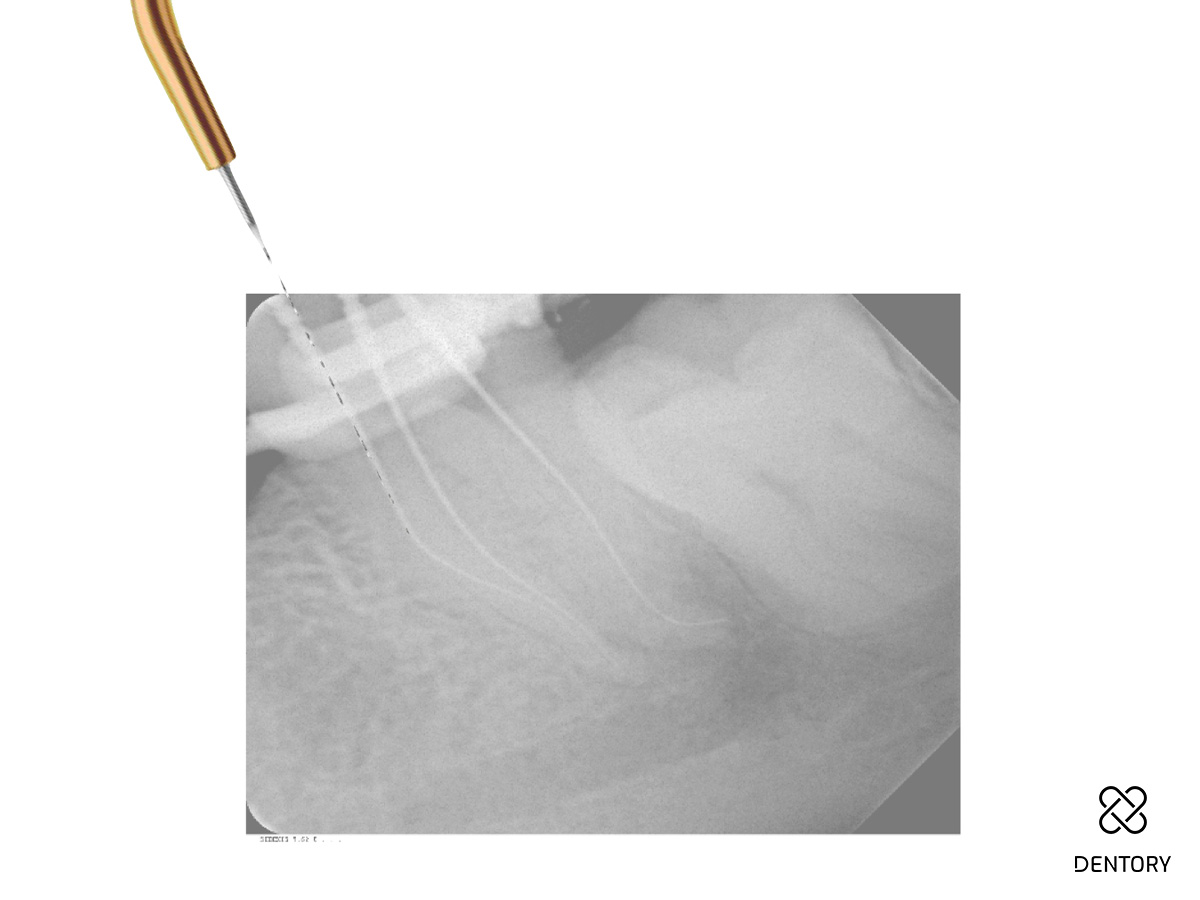

Abbildung 2

Röntgen-Messaufnahme: Aufgrund der Kanalkrümmung erfolgte die Messaufnahme bereits nach der Erstellung eines Gleitpfades bis ISO 10. Der mb und ml Kanal verfügen jeweils über ein separates Foramen.